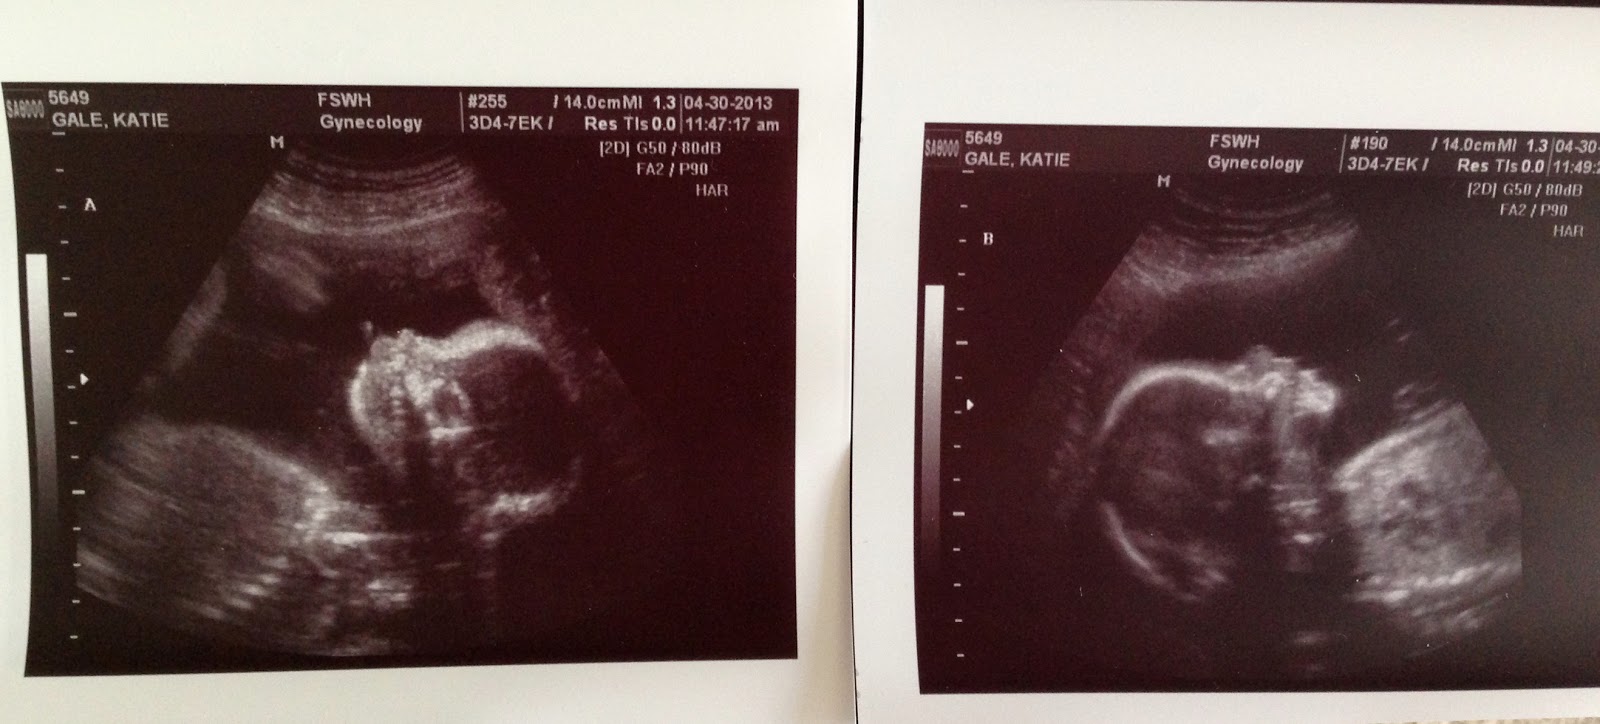

So, before the babies come,